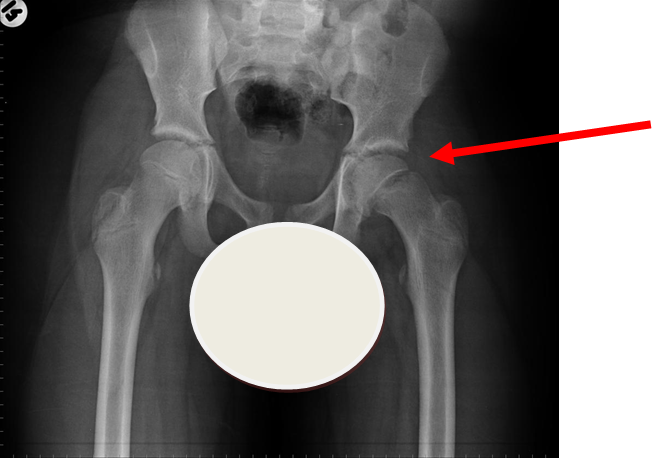

4. Slipped Upper Femoral Epiphysis (SUFE)

Lateral view of same patient as above

Case courtesy of Dr Gagandeep Singh, Radiopaedia.org. From the case rID: 7228

Usually occurs in late childhood / adolescence and is more common in boys than girls (2:1).  It also presents more commonly in children whose weight is above the 90th centile.  Bilateral in 25% of cases.  Onset can be acute or subacute (ie children may present with >1day h/o pain or limp).  Children may walk with an antalgic gait out-toeing, with shortening of the affected limb.  If the slip is acute, the child may be unable to walk.  Diagnosis is made radiologically and frog-lateral views are required as it may be missed on AP views.  Urgent orthopaedic opinion is required.  Unstable slips can lead to avascular necrosis of the femoral head.

Investigation

• X-ray - AP pelvis with frog lateral view (must be discussed with ortho 1st on call / ED consultant if child <8 years old)